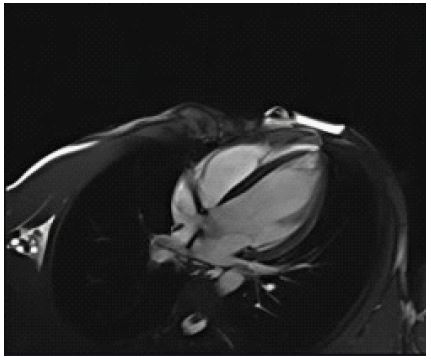

A 33-year-old female with no prior comorbidities presented with a seven-day history of high-grade fever, chills, rigors, dyspnea, and cough with borderline blood pressure requiring inotropes. Preliminary evaluation with ECG revealed sinus tachycardia and a 2D echo revealed global LV hypokinesia and severe Left ventricular dysfunction with LVEF of 30%. Initial laboratory investigations revealed elevated troponin with elevated NT-Pro-BNP suggestive of myocardial injury and acute heart failure, anemia (Hb: 9 g/dL), and elevated TSH (7.8 mIU/L), and mild renal dysfunction. The patient was admitted to the Intensive Care Unit and was treated for Heart Failure. A cardiac MRI was done, and it showed significant mid-myocardial Late Gadolinium Enhancement (LGE) in the LV free wall, sparing the endocardium and epicardium. While mid-myocardial LGE is commonly associated with myocarditis, it can also be seen in other conditions such as sarcoidosis, dilated cardiomyopathy, and Anderson Fabry disease. In this case, the findings were interpreted in conjunction with the clinical presentation, including recent febrile illness, elevated troponin, and rapid LV dysfunction. The imaging met the revised Lake Louise Criteria, supporting a diagnosis of probable myocarditis (Figures 1-3). Patient was started on IV Methylprednisolone 1 g daily for three days and then started on Oral prednisolone 1 mg/kg/day. Four days into her illness, she experienced two syncopal episodes and was found to have bradycardia with a heart rate of 30/min. An ECG revealed a complete heart block (Figure 4) with a wide-complex escape rhythm, and rising troponin levels indicated myocardial injury. A transvenous temporary pacemaker was placed, stabilizing her initially. A formal Transthoracic Echocardiogram (TTE) was performed after temporary pacemaker placement, which revealed the same moderate to severe LV dysfunction and no additional complications. Sarcoidosis was considered due to mildly elevated ACE levels (61 U/L), but further testing, including CT chest, EBUS, and node biopsy, was not feasible due to the patient’s rapid deterioration. Giant cell myocarditis, though rare in young patients, was also considered, given the aggressive course and refractory ventricular arrhythmias. A comprehensive evaluation could not be conducted due to the rapid progression of the disease. However, viral myocarditis remained the most likely etiology based on clinical presentation, negative H1N1 swab, and absence of autoimmune markers (ANA: 1:40, dsDNA < 30 IU/mL) (Table 1). After TPI, she developed slow ventricular tachycardia (130/min) (Figure 5), which persisted despite multiple attempts at overdrive pacing. Amiodarone was initiated (150 mg IV bolus, followed by 1 mg/min for 6 hours, then 0.5 mg/min for 18 hours), but VT remained refractory. Lidocaine (1.5 mg/kg IV bolus, followed by 1 mg/min infusion) was added, but the arrhythmia remained refractory. Overdrive pacing was attempted but was discontinued after the onset of Polymorphic Ventricular Tachycardia (PMVT). Given the fulminant nature of myocarditis, catheter ablation was not attempted, as the arrhythmogenic substrate was likely diffuse rather than focal, reducing the likelihood of procedural success. The patient continued to deteriorate into refractory cardiogenic shock despite maximal inotropic and antiarrhythmic therapy. She experienced cardiac arrest and could not be resuscitated. Referral for mechanical circulatory support (ECMO) was considered, but stabilization for transfer was not possible given the rapid decline. Post-mortem biopsy was not performed due to lack of consent.

Figure 1: Short axis phase contrast T1 sequence shows mid myocardial late gadolinium enhancement along the left ventricular free wall with sparing of endo & epicardium.